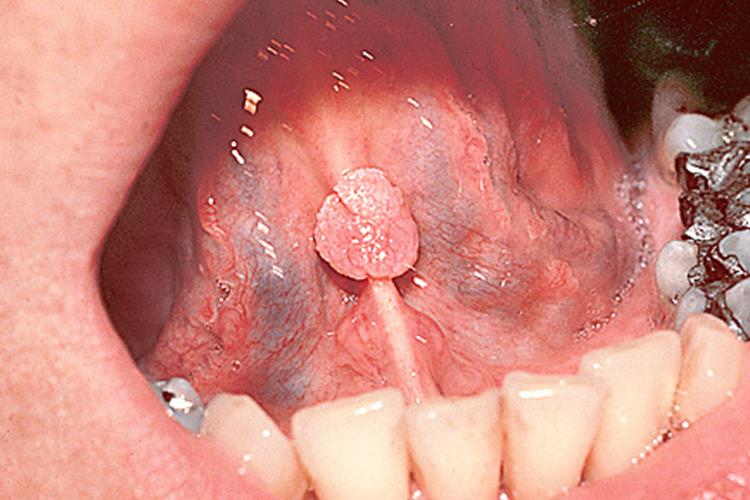

特殊部位疣:口腔内也可出现类似于生殖器疣的疣状损害,初始为丘疹状,逐渐增大至乳头或菜花样。